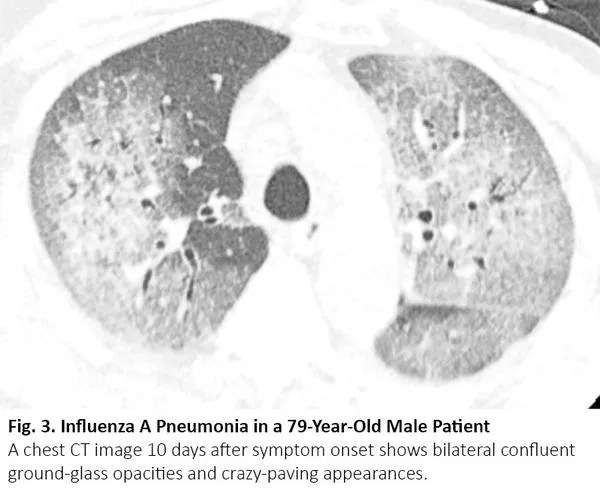

化疗、免疫治疗可引起药物性肺炎,导致CT呈现间质性肺部疾病的影像学表现。12最常见的类型是隐源性机化肺炎,其次是非特异性间质性肺炎、超敏性肺炎和急性间质性肺炎。13其中,隐源性机化肺炎、非特异性间质性肺炎的影像学表现可与COVID-19肺炎相似(图4),反之亦然。14

图4. 一位71岁肺鳞癌男性患者出现纳武利尤单抗治疗导致的肺炎